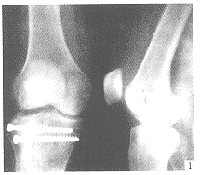

(6)脛骨平台骨折內固定:

①劈裂骨折(Ⅰ型):先整復骨折遠端,再做由後向前上推擠整復骨折近端,用克氏針暫固定,骨折近端用拉力松質骨螺釘沿平台關節面軟骨下至內側皮質固定,骨折遠端可用拉力皮質骨螺釘穿內側皮質骨固定。